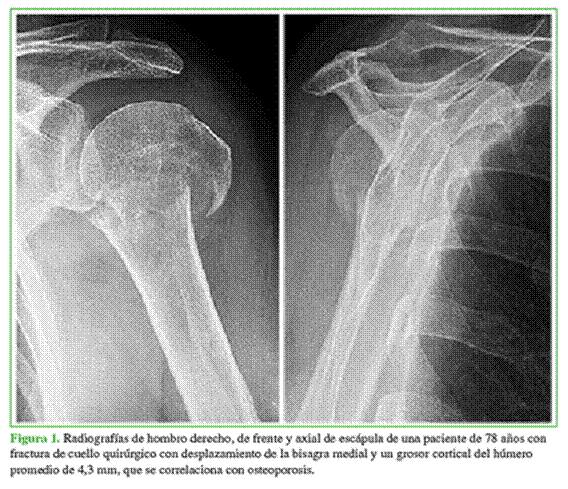

Las indicaciones para recibir este tratamiento fueron: fracturas de cuello quirúrgico con conminución o insuficiencia de la bisagra medial y pacientes con signos indirectos de osteoporosis utilizando el método de medida del GCHP de Tingart modificado, con valores <6 mm (Figuras 1 y 2).13

Ocho de los 12 pacientes incluidos tenían fracturas grado IV y cuatro, grado III de la clasificación de Resch. Se observó insuficiencia de la bisagra medial en ocho casos (67%), un GCHP <6 mm en tres casos (con bisagra medial conservada) y la combinación de ambos factores en un paciente. El valor promedio del GCHP preoperatorio fue de 6,6 mm (rango 4,3-7,95).